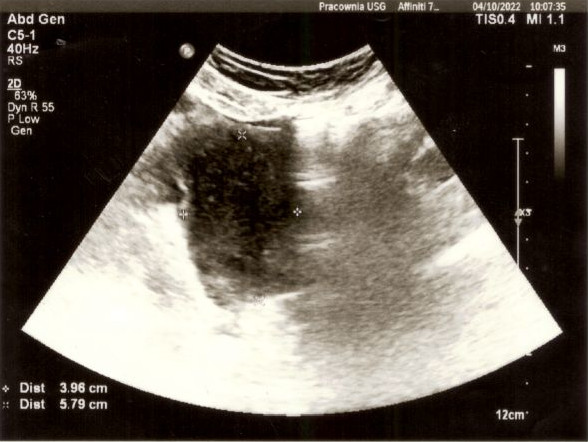

Minął prawie rok od dnia, w którym poszedłem na spotkanie z Wojownikami. Zbliżało się kolejne spotkanie ogólnopolskie, również w Bydgoszczy. Moja małżonka w międzyczasie idzie na badanie, które systematycznie musi powtarzać co ok 6 miesięcy. Jakiś czas temu wykryto u niej polipy na woreczku żółciowym, więc od paru lat musi je kontrolować. Głównie też ze względu na to, że może być obciążona genetycznie (ojciec Karoliny zmarł na raka). Lecz nie to było naszym utrapieniem. Podczas wizyty kontrolnej na USG wyszło coś jeszcze. Oczom lekarza ukazała się duża zmiana na macicy. Doskonale widać ją było na zdjęciu USG. Lekarz zasugerował pilną konsultację ginekologiczną. Gdy usłyszałem te wieści od mojej kochanej żony i obejrzałem zdjęcie USG, zamurowało mnie i nie wiedziałem, co powiedzieć (zmiana miała prawie 6x4cm widać ją na poniższych zdjęciach). Ogarnął mnie smutek i żal.